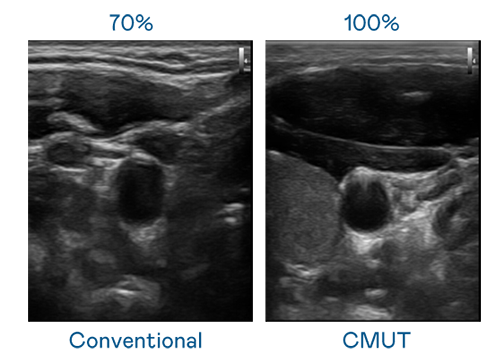

CMUT 技术是一种用电容式微机电元件来产生超音波讯号的技术。与传统 PZT 压电式技术相比,CMUT 频宽增加 30%,更宽频的超音波讯号让影像解析度大幅提升,是实现高影像品质医疗超音波扫描、促进精准医疗发展的关键技术。

大频宽带来超清晰影像

超音波影像的解析度高低,首先取决于探头能发出的讯号频宽。星空无限mv在线看免费版中文版在线看 CMUT 可提供高清晰的超音波讯号,提供高频宽、高灵敏度、影像纹理细节更高的超音波影像,协助医护人员缩短影像判读时间及利用精准的医疗影像进行诊断。